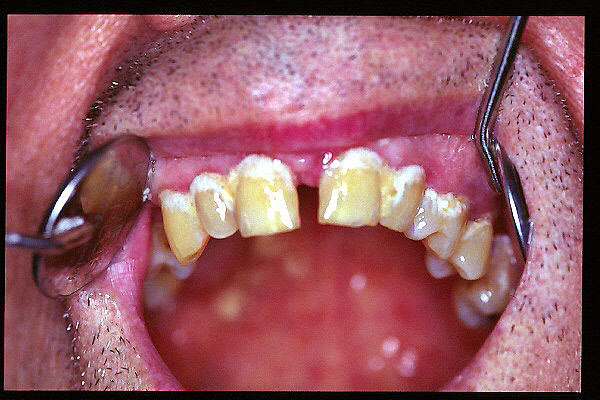

CM Extrusión de incisivos inferiores por falta de contactos oclusales